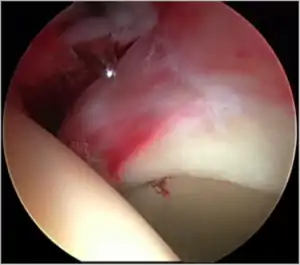

Figure 5. Portal placement under direct vision. The instrument is entering the joint through the hip capsule, between the femoral head (on the left) and acetabular labrum (on the right)

The acetabular labrum is a fibrous structure, which surrounds the femoral head. It forms a seal to the hip joint,[15] although its true function is poorly understood. Recent evidence has demonstrated that this hydraulic seal is vital for maintaining stability of the ball and socket joint [16] and reducing contact pressures of the femur to the acetabulum.[17] The labrum has also been shown to have a nerve supply and as such may cause pain if damaged.[18] The underside of the labrum is continuous with the acetabular articular cartilage so any compressive forces that affect the labrum may also cause articular cartilage damage, particularly at the junction between the two, the chondrolabral junction. The labrum may be damaged or torn as part of an underlying process, such as FAI or dysplasia (shallow hip socket), or may be injured directly by a traumatic event. Depending on the type of tear, the labrum may be either trimmed (debrided) or repaired. Removing or debriding the labrum is becoming less popular as the latest research shows that results are more predictable in the long term if the labrum can be repaired. Various techniques are available for labral repair, mainly using anchors, which may be used to re-stabilise the labrum against the underlying bone, allowing it to heal in position.